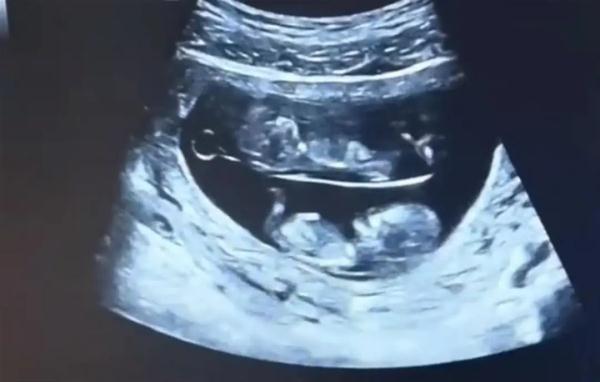

有網友曬出了他們的B超照

十分有趣

視頻中

兩個寶寶在母親的肚子里

呈上下分布

并且還不停踢動

“從網友發布的視頻來看,兩個胎兒在媽媽肚子里各占一間房,這是很常見的,是典型的‘雙羊’。”朱霞說,但像這么規整地看似“上下鋪”的,確實很少見,80%至90%是左右“分房”,雙胞胎在孕媽子宮內也會呈現不同的姿勢。